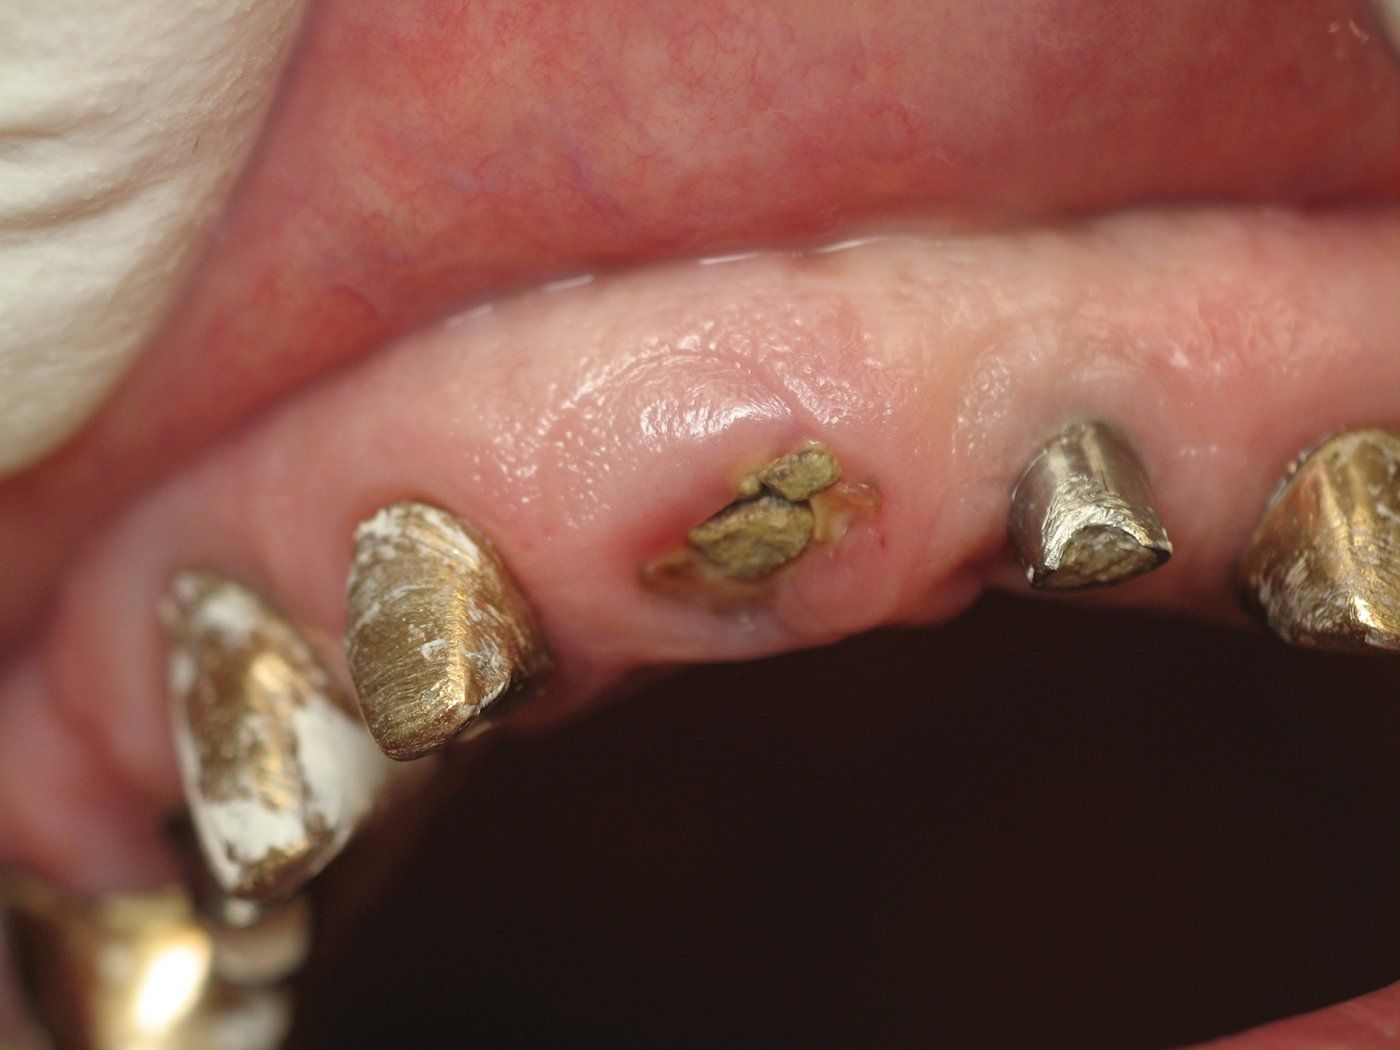

One day a 50 year-old patient and dentist friend of mine, (who already has multiple dental implants) came to my office and presented with a non-restorable fractured tooth number 8 (Figure 1). As you can see from the photograph, this looked to be a complicated extraction. As always, my treatment plan consists of proper imaging. With dental implant cases it usually involves the i-CAT. (Figure 2)